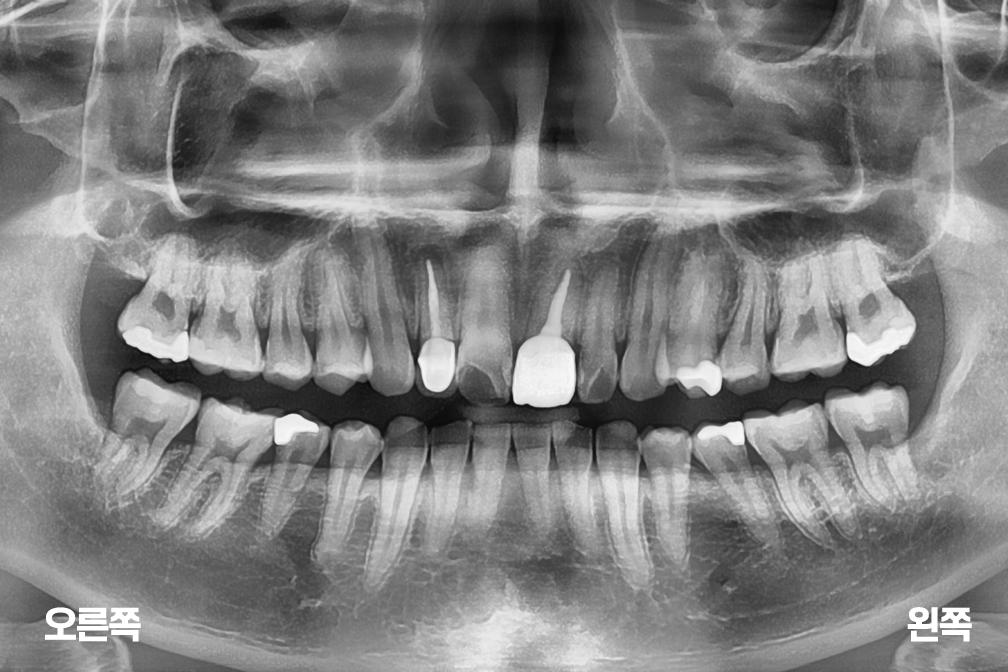

사랑니발치 사랑니 3개 발치

사랑니 발치

위 전후사진은 이미지사진으로 실제 눈으로 보는 것과는 다를 수 있으며, 환자의 치아상태과 방법에 따라 치료결과가 다를수 있습니다.